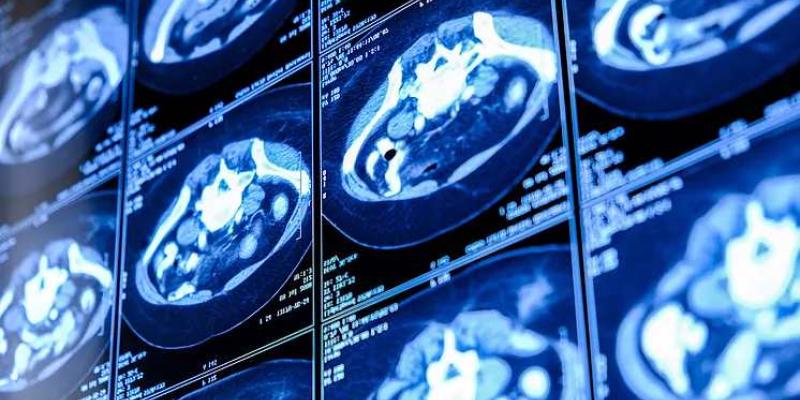

Imagen de un escáner

El proyecto piloto Cassandra busca revolucionar la detección precoz de enfermedades respiratorias mediante una tomografía computerizada de baja dosis del tórax. Esta prueba, que dura alrededor de 30 minutos, ofrece a los especialistas la capacidad de identificar rastros de cáncer, patologías respiratorias y otras anomalías en la región torácica, permitiendo un diagnóstico temprano que podría salvar vidas.

La tomografía computerizada de baja dosis del tórax es una técnica sencilla, rápida, indolora y cómoda para los pacientes. Esta prueba, que no requiere contraste intravenoso, utiliza una radiación mucho menor que las técnicas convencionales, siendo una herramienta eficaz para evaluar diferentes aspectos del pulmón, incluyendo nódulos, calcificaciones arteriales, enfisema pulmonar y osteoporosis, convirtiéndose en la opción diagnóstica más completa para el estudio pulmonar.